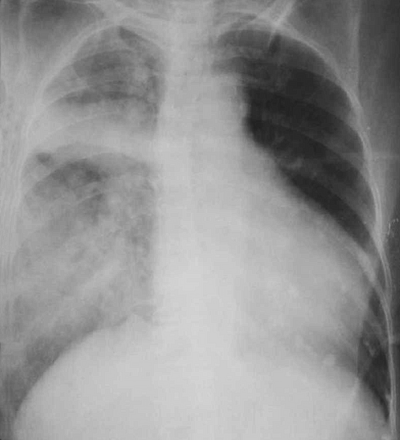

• Рентгенография, ультразвуковое исследование грудной клетки: застой в легких.